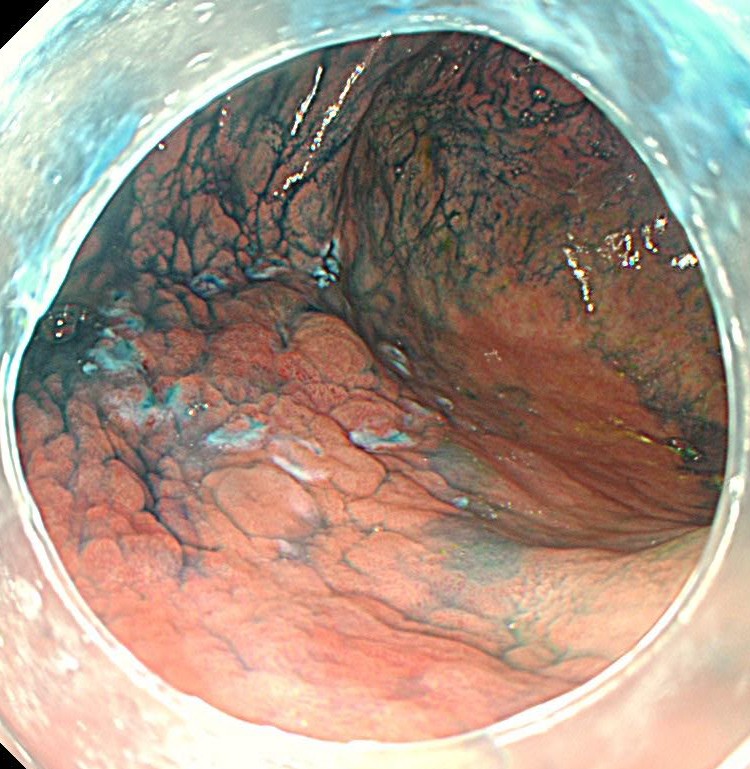

がん部を取り囲むようにマーキングをします。フラッシュナイフ2.5を用いています。電気メスはVIO300を使用しています。

フラッシュナイフを用いて全周切開します。粘膜下の局注は生理食塩水のみを使用しています。

粘膜下層剥離術を開始します。

フラッシュナイフで剥離をすすめます。VIO300のスイフトコアグレーションモードを使用しています。